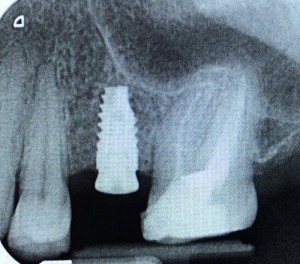

Complications and survival rates of implants from 9 to 15 years follow-up

Dental implantology is currently a routine therapy performed on young patients but also on older patients, with or without systemic diseases. Despite the fact that dental implant therapy has been...